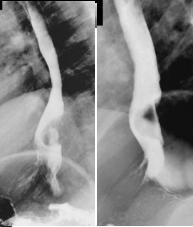

TOGD en double de

contrast |

Images claires

arrondies diffuse le long de oesophage . Mouvement

de contraction oesophagien normale . |